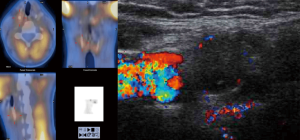

In case 2, a BNE was performed for secondary HPT with the identification and excision of three hyperplasic glands; the left inferior parathyroid gland was not found. A repeat parathyroid scintigraphy with an oblique projection disclosed a left UPA (Figure 2) that was excised at reoperation. An autotransplantation to the forearm was performed. He later received a kidney transplant.